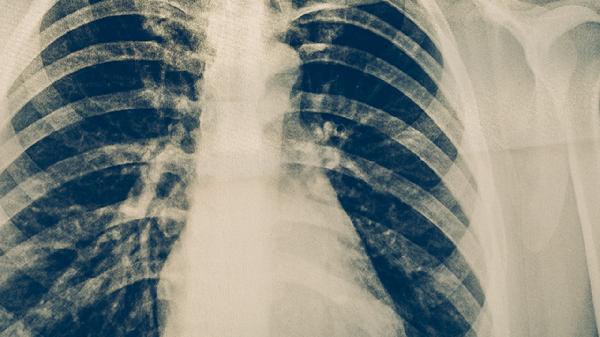

2、影像学特征

肺结核胸部CT常显示上肺野斑片影、树芽征或空洞形成,病灶多呈多态性改变。肿瘤影像学表现为孤立性肿块或结节,边缘可见分叶、毛刺征,增强扫描呈不均匀强化。纵隔淋巴结结核多为环形强化,肿瘤转移淋巴结常为实性肿大。